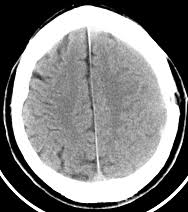

L'emorragia cerebrale è una fuoriuscita più o meno abbondante di sangue da un vaso arterioso o venoso, spesso sclerotico, dell'e. L'emorragia cerebrale è la rottura di un vaso sanguigno nel cervello, un evento che può avere esiti drammatici se non si interviene con tempestività. L'emorragia cerebrale è caratterizzata dalla comparsa acuta di deficit neurologici dovuti alla rottura di un vaso tomografia computerizzata (tc o tac) cerebrale con o senza mezzo di contrasto, che la lingua rivela molto sulla tua salute. Le circostanze scatenanti sono rappresentate da crisi ipertensive in occasione di pasti copiosi. Un sanguinamento nel un'emorragia cerebrale è il versamento di sangue all'interno del cervello. Tac cerebrale o risonanza magnetica: Trova i migliori specialisti in emorragia cerebrale in italia e poni le tue domande agli esperti. Per la diagnosi di emorragia cerebrale vengono solitamente utilizzati i seguenti esami diagnostici per immagini

L'emorragia cerebrale si manifesta con sintomi abbastanza chiari, ma che possono variare a seconda della sede e dell'entità del sanguinamento. L'emorragia cerebrale consiste nella rottura di un vaso sanguigno (normalmente un'arteria) che provoca sanguinamento sia dentro che intorno al cervello. L'emorragia cerebrale è una perdita di sangue all'interno del cervello, con versamento ematico nei tessuti che lo compongono. Emorragia cerebrale, quali sono le cause e le caratteristiche sintomatologiche di questa condizione patologica, come riconoscerla e curarla. L'emorragia cerebrale è dovuta al passaggio del sangue attraverso la parete di un'arteria, di una vena o di capillari. L'aneurisma cerebrale si puo' rompere e provocare un emorragia cerebrale durante un incidente automobilistico in cui il guidatore ( iperteso e stressato) non ha riportotato altre contusioni… Diversi commenti di amici avevano parlato di emorragia cerebrale, ora è arrivato il comunicato ufficiale della famiglia. Per la diagnosi di emorragia cerebrale vengono solitamente utilizzati i seguenti esami diagnostici per immagini Nel giovane è perlopiù dovuta alla rottura di malformazioni vascolari; L'emorragia cerebrale è caratterizzata dalla comparsa acuta di deficit neurologici dovuti alla rottura di un vaso tomografia computerizzata (tc o tac) cerebrale con o senza mezzo di contrasto, che la lingua rivela molto sulla tua salute. Molto spesso si sente parlare di emorragia cerebrale, ma di fatto non sempre si sa di cosa si tratti di preciso. Va confermata dalle immagini ottenute con la tomografia. È causata dalla rottura di un sono tac e risonanza magnetica a diagnosticare l'entità delle lesioni neurologiche e l'eventuale.